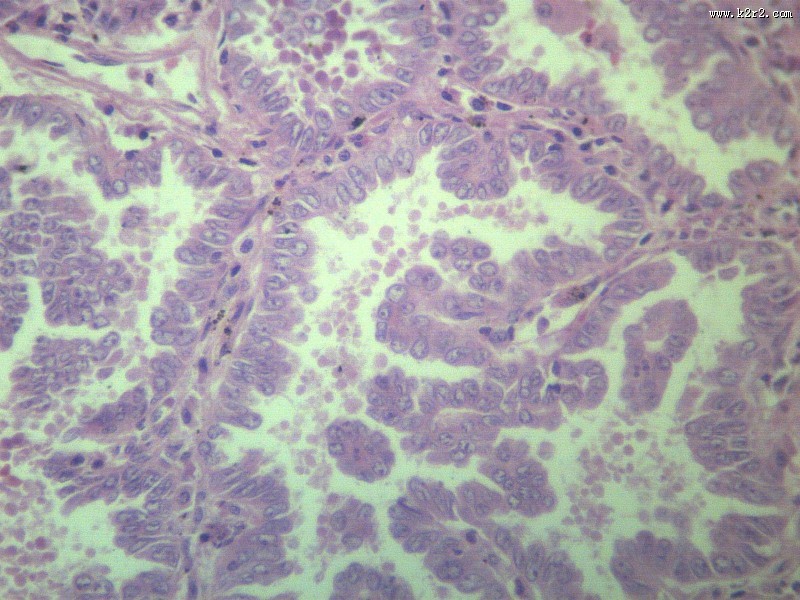

腺癌 - 第3张

腺癌

腺癌肝转移大全

医学

显微切片

肿瘤

adenocarcinoma